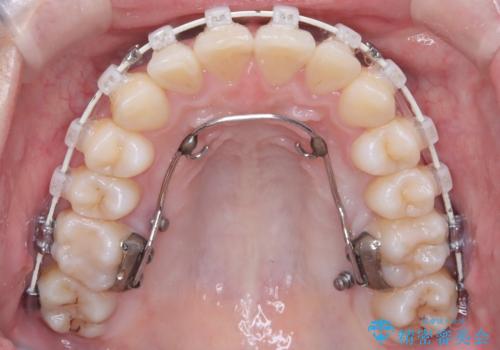

- 患者様は、前歯の重なり(叢生)が気になるとのことでご来院されました。診断の結果、奥歯を後方に移動することで前歯にスペースを確保し、非抜歯で歯列を整える方針としました。治療には審美性の高いホワイトワイヤーを使用し、奥歯の遠心移動にはリンガルアーチを装着しました。治療期間は約2年を予定し、月に一度の調整を通じて歯の動きを細かく管理しました。

非抜歯矯正は、歯を抜かずに自然な歯列を作るため、歯列全体のバランスを考慮する必要があります。本症例では、リンガルアーチによる奥歯の遠心移動を用いましたが、初期段階で軽い違和感を覚える方もいらっしゃいます。そのため、装置装着後のケアや食生活について詳しく説明を行い、患者様にも協力いただきました。また、審美ワイヤーを使用することで、日常生活での見た目のストレスを軽減し、治療を快適に進めることができました。